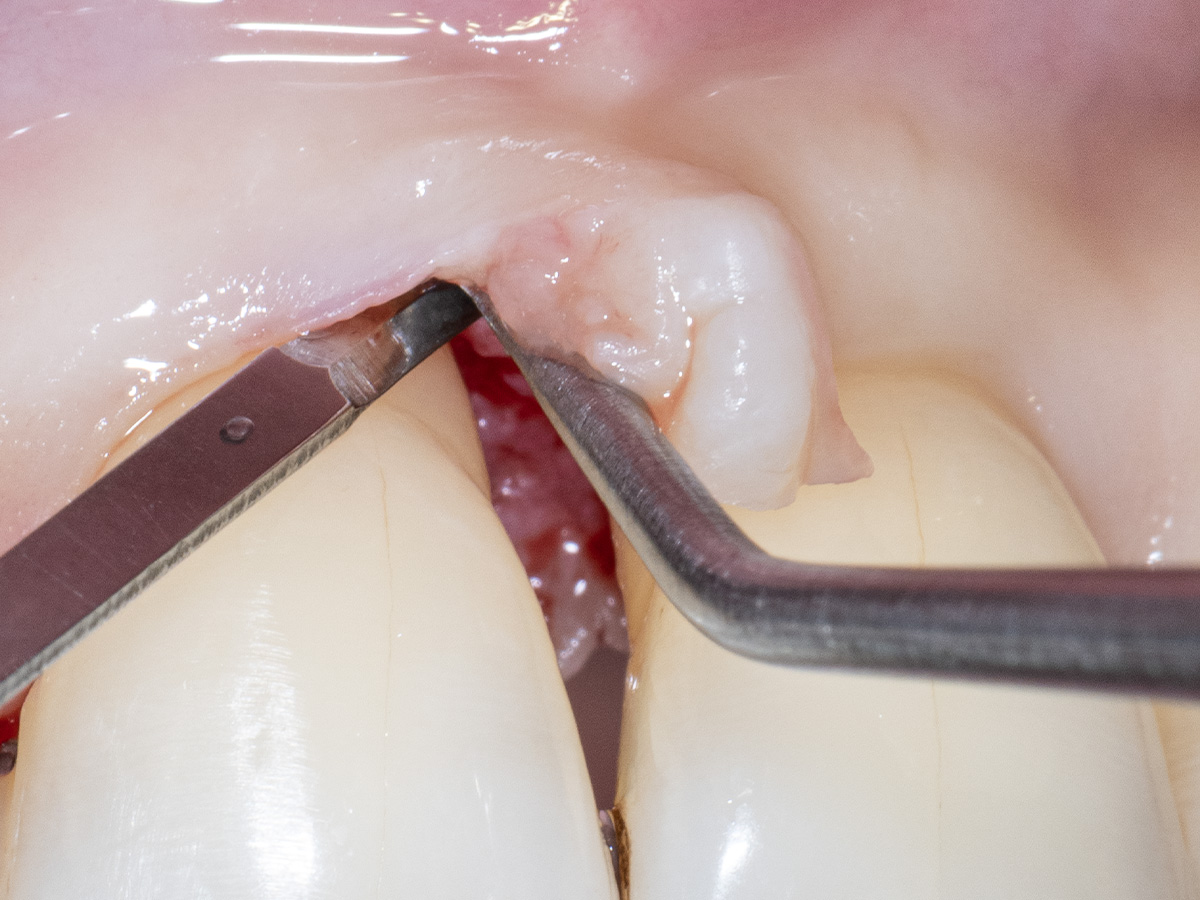

Aufgrund der hohen Lachlinie haben wir uns für eine horizontale Inzision durch die Papillenbasis auf der palatinalen Seite sowie intrasulkuläre Inzisionen um die Nachbarzähne entschieden. Auf diese Weise können Oberflächeninzisionen auf der bukkalen Seite, die zu sichtbarem Narbengewebe führen können, vermieden werden.

Folglich wurde ein palatinaler Mukoperiostlappen eleviert, um Zugang zum Defekt zu erhalten.

Um den mesiobukkalen Aspekt des Defekts zu erreichen, wurde ein zweiter Lappen mit einer ultradünnen und biegbaren Keydent Spin Blade 360 präpariert, die an die jeweilige anatomische Situation angepasst werden kann und präzise intrasulkuläre Inzisionen im Interproximalraum sowie ein vorsichtiges Abtrennen des entzündlichen Infiltrats vom Weichgewebe und ein anschließendes sanftes Herauslösen auf die bukkale Seite ermöglicht.